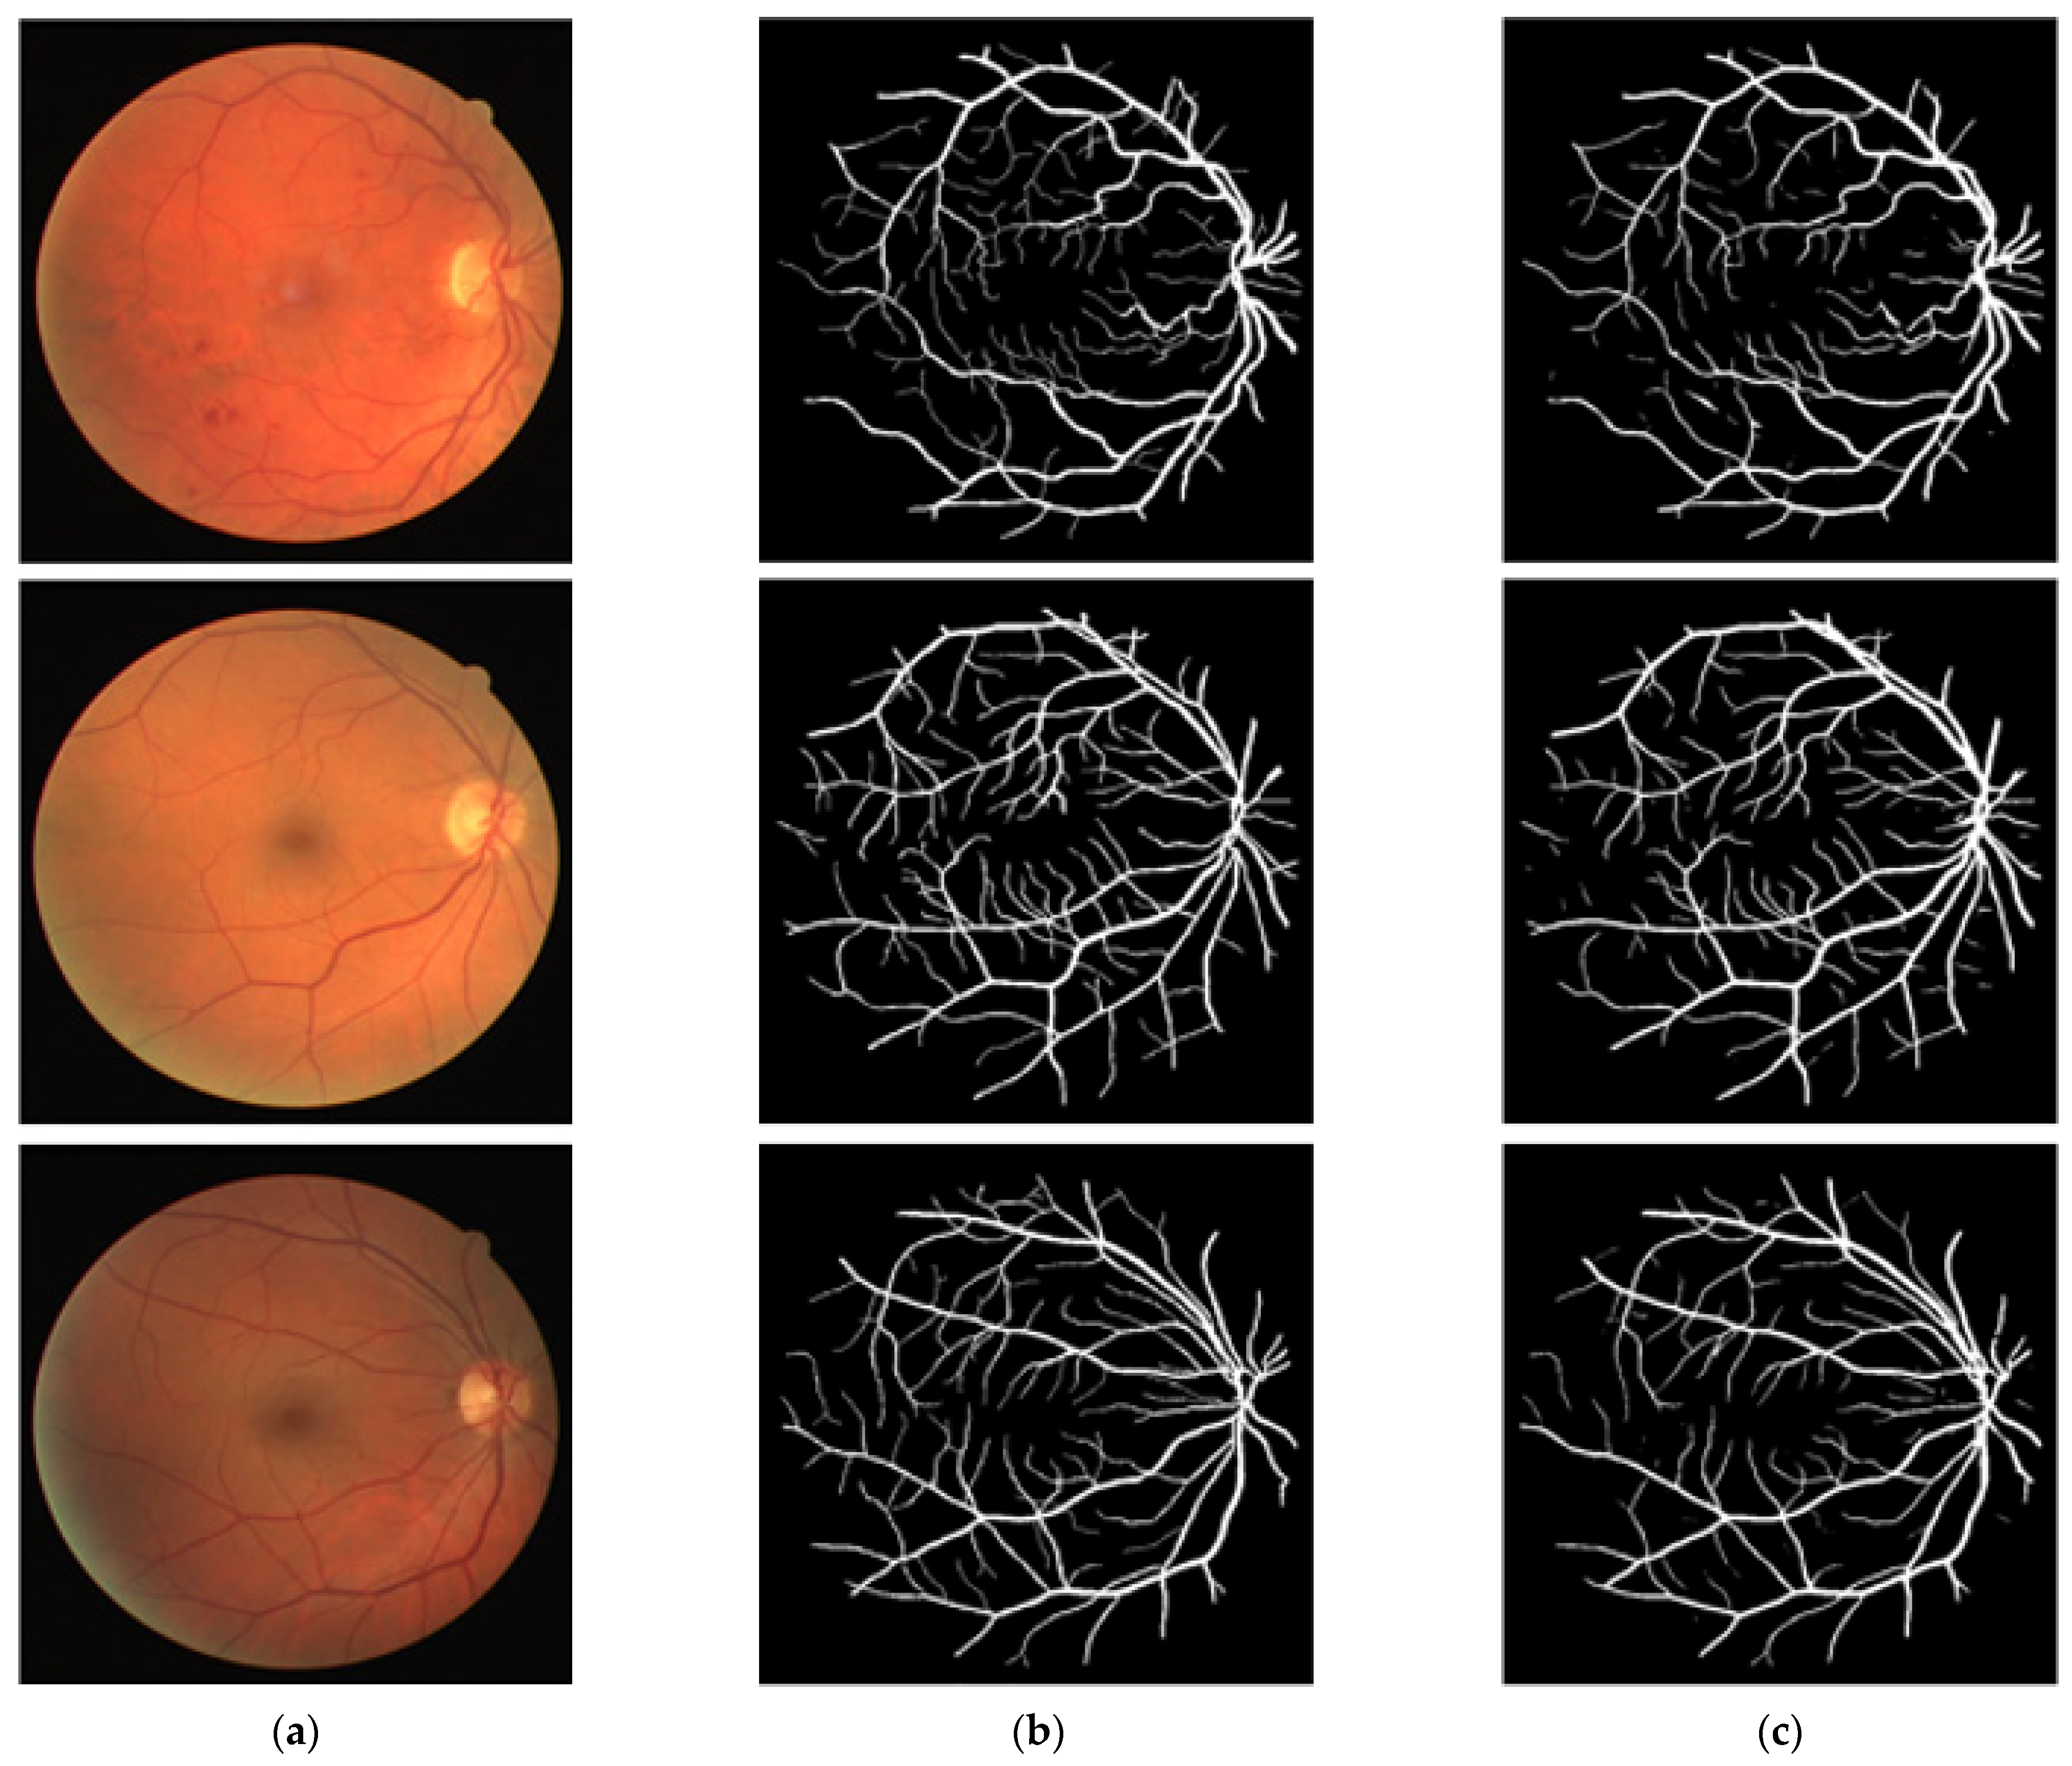

3.4. Visual Results of the Proposed Method for Vessel Segmentation

In this section, the vessel segmentation visual results are presented for the publicly available DRIVE, STARE, and CHASE-DB1 retinal image datasets. The output of the network is a binary mask that is compared with an expert annotation mask for evaluation. Figure 9, Figure 10 and Figure 11 display the visual results of the proposed method; Figure 9, Figure 10 and Figure 11 display the (a) original input image, (b) expert annotation mask, and (c) predicted mask for the proposed method.

Figure 11.

Visual results of the proposed DSA-Net using CHASE-DB1: (a) Original input image, (b) Expert annotation, and (c) Predicted image mask by DSA-Net.